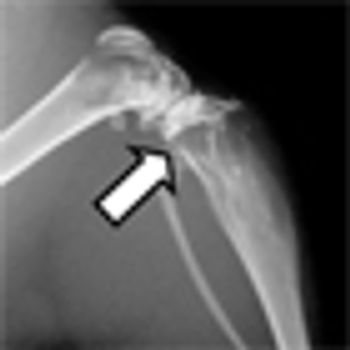

This slide show features images of diffuse osteoblastic bone metastases in a 70-year-old advanced prostate cancer patient, bone metastases in the vertebral column of a kidney cancer patient, and more.

A mouse model of bone metastasis can be used to follow real-time response to therapeutics in preclinical development, such as cabozantinib, according to results presented in the poster session of the 2013 AACR annual meeting.

Imaging is important for both the diagnosis and management of prostate cancer. Standard techniques used in everyday clinical practice depend on the stage of the disease. Several new experimental modalities are currently in development to better identify and diagnose patients with progressive disease.